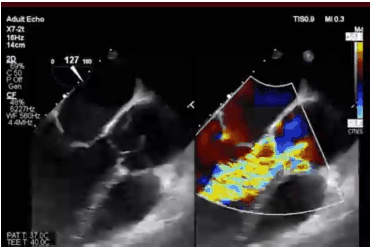

Paciente homem, 85 anos, portador de estenose aórtica grave e alto risco cirúrgico, submetido a implante valvar aórtico percutâneo (TAVI). Imediamente após a liberação da válvula, foi submetido a ecocardiograma transesofágico que mostrou leve refluxo.

A seguinte imagem foi obtida.

Nesse caso, nota-se regurgitação